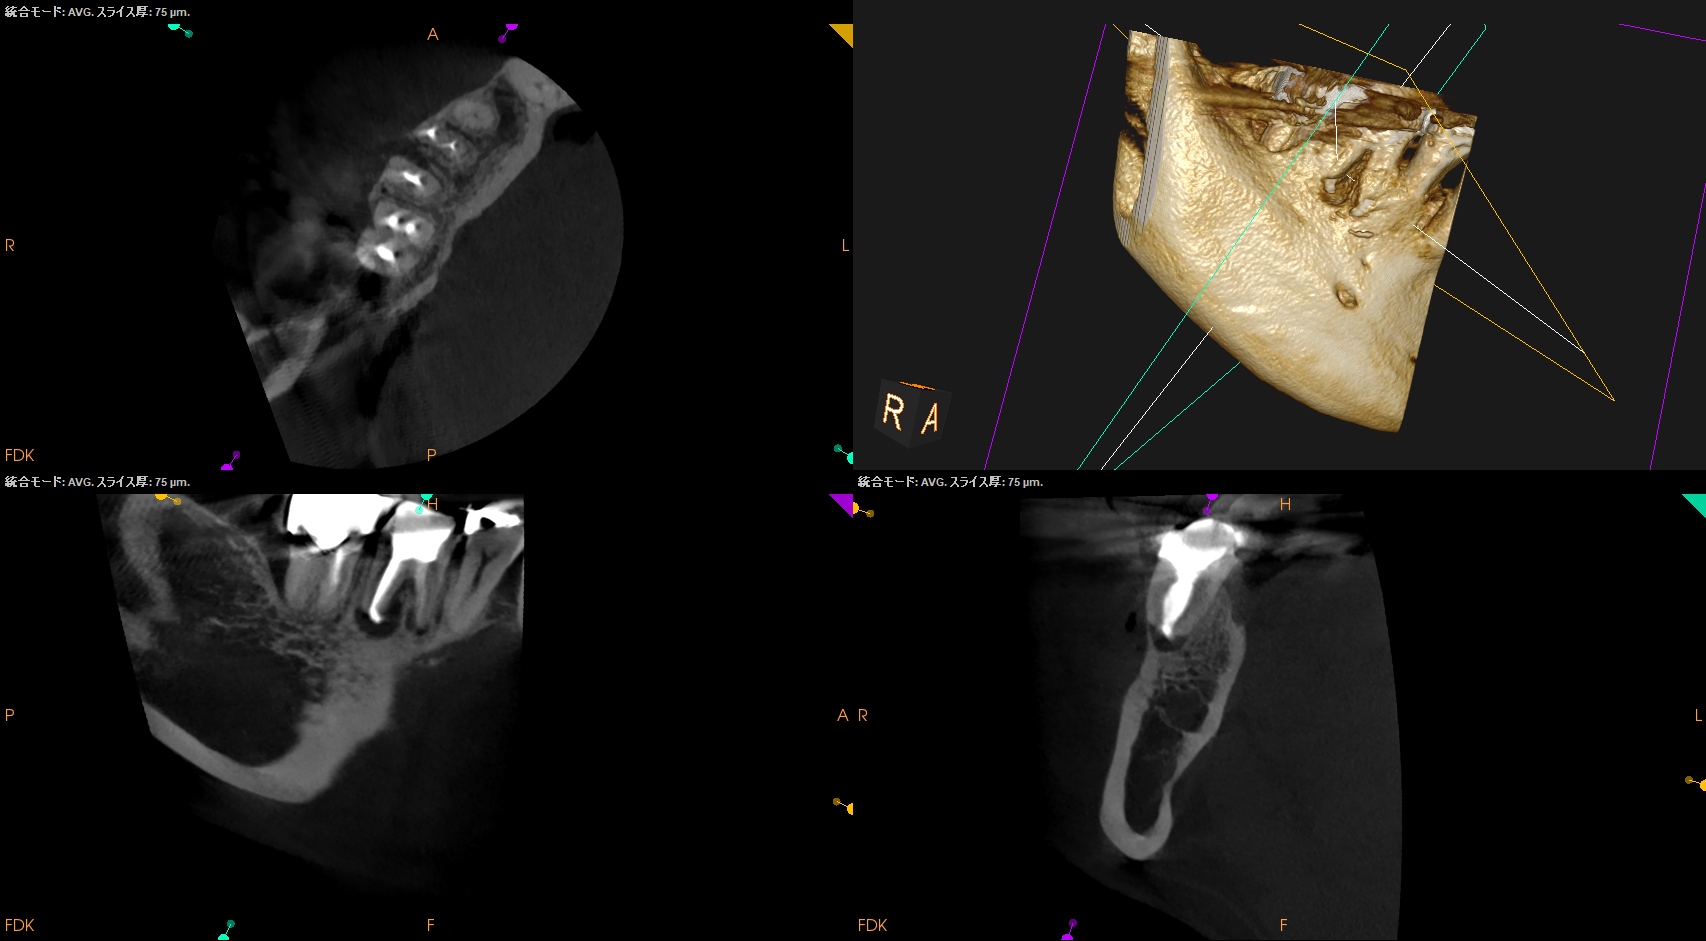

CBCT(2025.9.16)

#30

MB

ML

D

B

頬側の皮質骨が裂開していることが圧痛の原因だろう。

が、Suns tractがないのでApicoectomy!というよりは再根管治療だろう。

ということで、別日に再根管治療へ移行することになった。